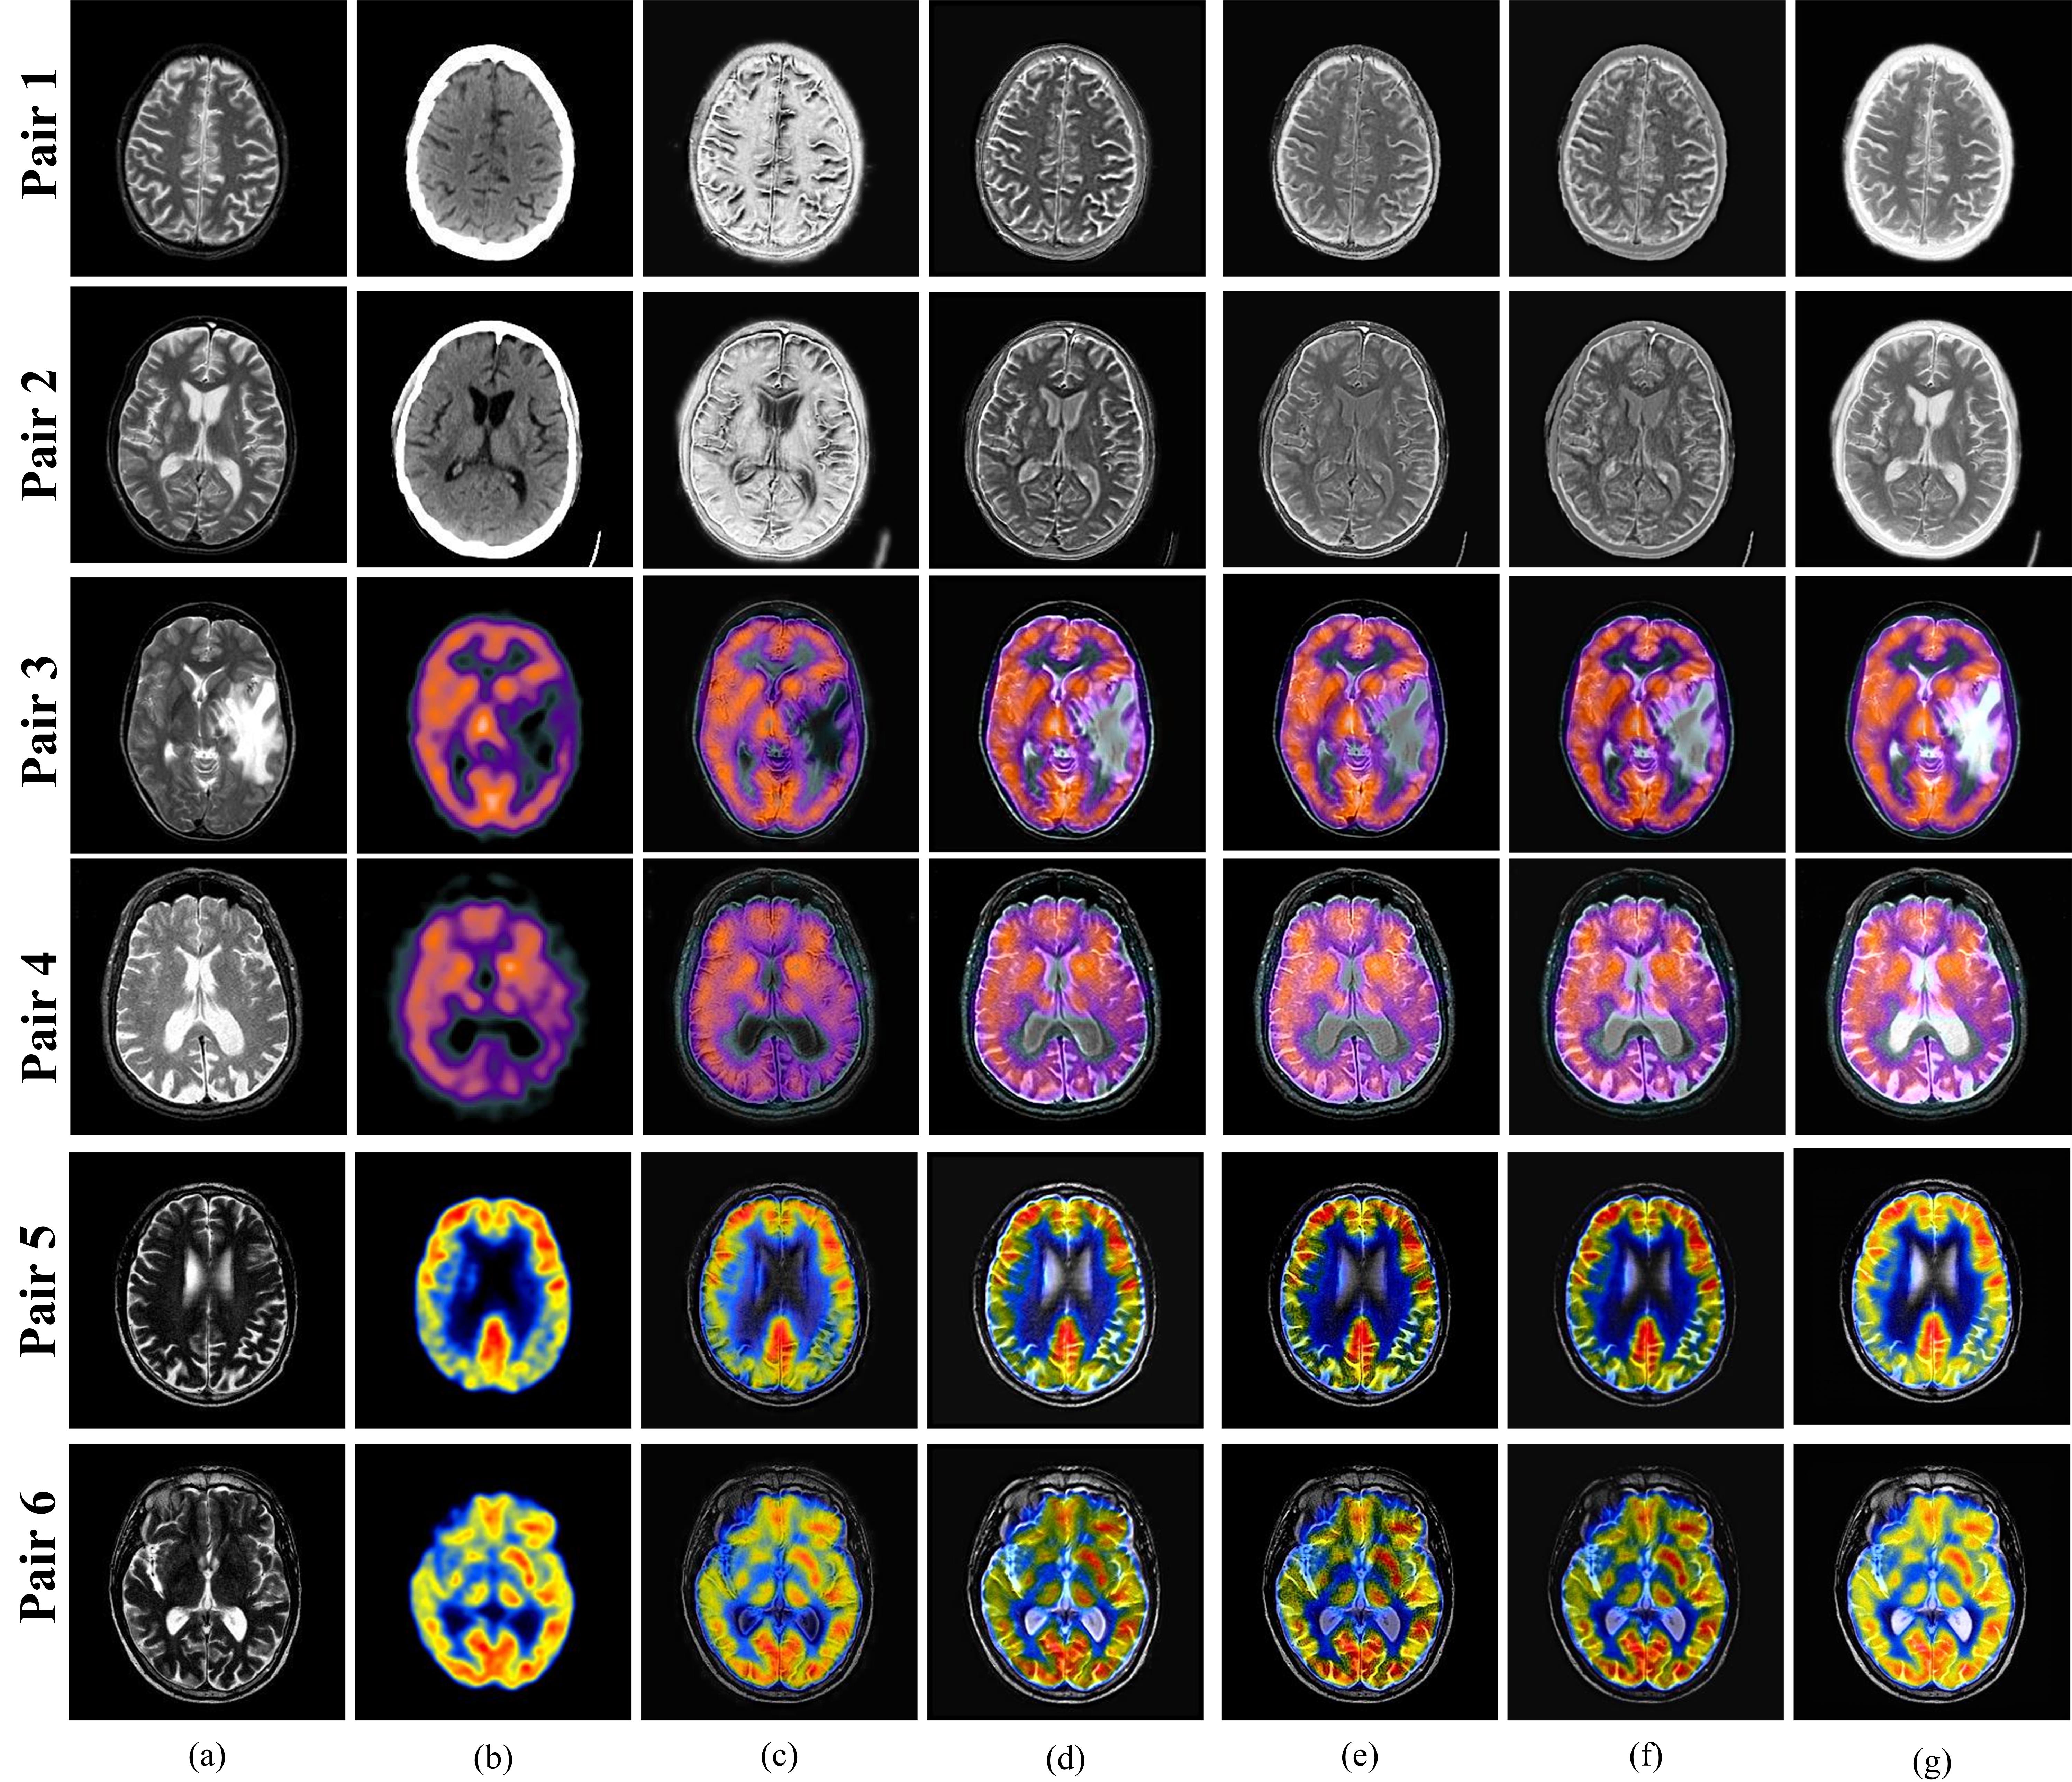

Refer to caption

Figure 4: Subjective comparison of fusion results (a) source image 1, (b) source image 2, (c) DDcGAN-2020[10], (d) DSAGAN-2021 [11], (e) SDNet-2021[9], (f) U2F-2022[8], (g) proposed method

Fig. 4 shows six image pairs along with the fused images obtained by the four SOTA fusion methods and the proposed method. For MR-T2-CT fusion (pair 1 and 2), the DDcGAN-2020 [10] method gives fused images with visible artifacts resulting in poor visual results (refer Fig. 4(c)). The DSAGAN-2021 [11], SDnet-2021 [9] and U2F-2022 [8] methods offer a better representation of soft tissue details of MR-T2 image, however, lose the hard tissue information present in the CT image, as a result, the skull boundary is not highlighted well which can be visualized from Figs. 4(d)-(f). On the other hand, Fig. 4(g) shows that the proposed method yields a fused image with effective preservation of intensity and textures of both hard and soft tissues. For MR-T2-SPECT image fusion (pair 3 and 4) depicting a case of metastatic bronchogenic carcinoma, DDcGAN-2020 [10] fusion method ceases to preserve the textural information of the MR-T2 image. The SDNet-2021 [9] and U2F-2022 [8] methods capture the gradients of the soft tissues, however these methods are not able to preserve the color maps of the SPECT image, leading to reduced contrast and visually inferior fused images. Though the DSAGAN-2021 [11] method and the proposed method offer better contrast but the tumor is highlighted and demarcated better in the fused images obtained by the proposed method (refer to Fig. 4(a), (d) and (f)). For MR-T2-PET image fusion (pair 5 and 6), it can be visualized from Fig. 4, that the proposed method offers better integration and retention of both the anatomical and functional details of the tissues in terms of contrast, edge preservation, spatial and color fidelity as compared to other SOTA fusion methods.